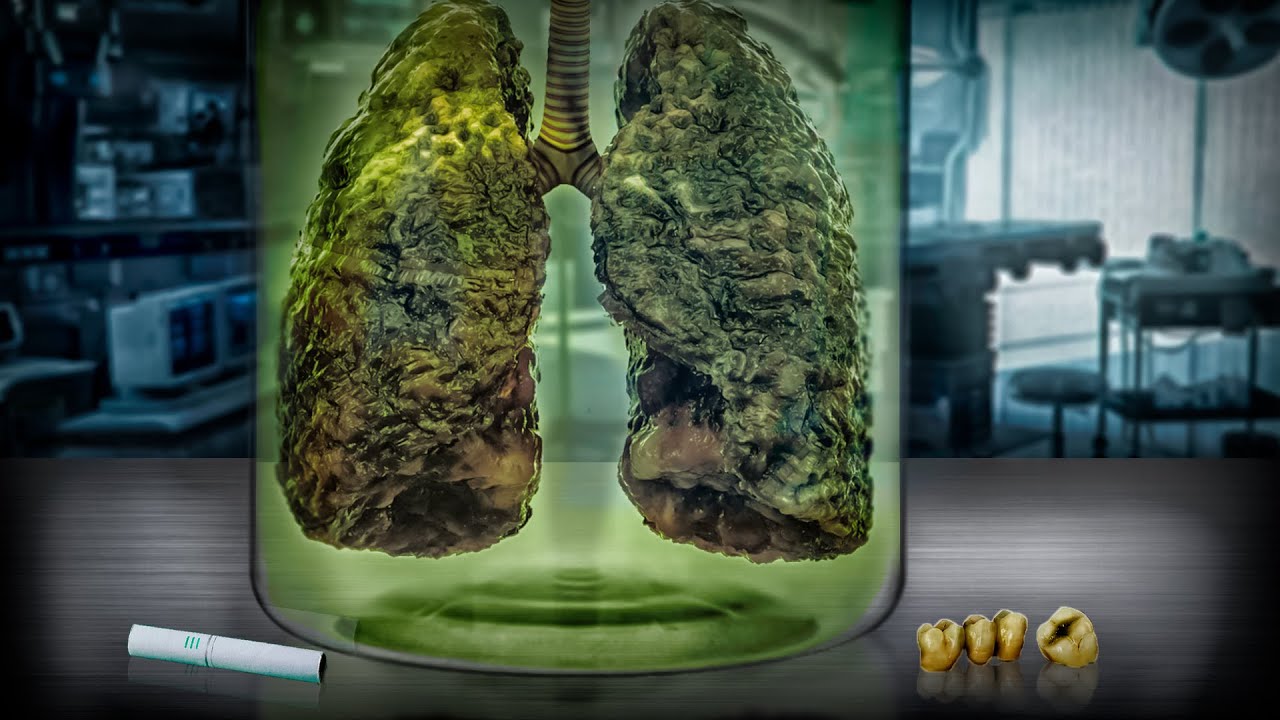

Влияние вейпа на легкие: Фотографии и исследования

Раздел: Визуальный дайджест